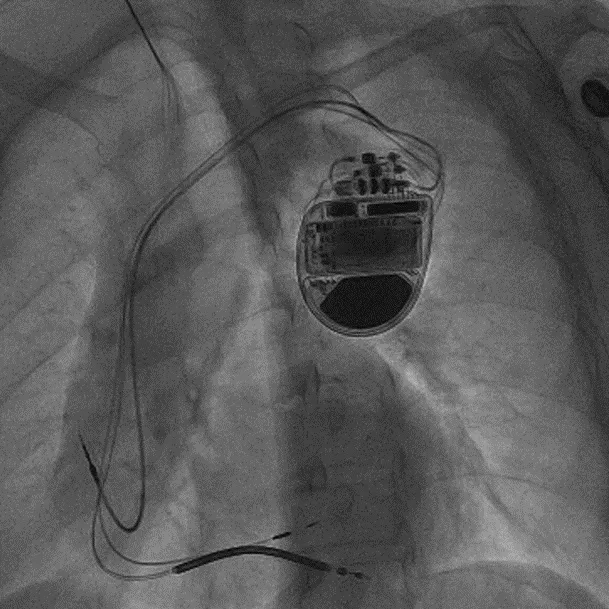

拔除无导线起搏器后植入左束支CRTD的术后影像

术前,汤宝鹏教授带领治疗团队对文献进行了详细查阅,对病情进行了充分而细致地评估,对术中可能出现的各种风险做好了各项应急预案。术中,手术团队使用圈套器成功抓捕无导线起搏器Micra尾端并顺利拔除,同时给患者植入左束支心脏再同步起搏除颤器。手术顺利,患者术后恢复良好。

目前,全国范围内针对非急性期无导线起搏器移除还没有足够的经验,个案移除均为术中或术后短期微脱位,起搏阈值升高,无导线起搏器未形成内皮化而被包裹。此次患者体内植入时间超过两年的无导线起搏器已部分形成内皮化和被包裹,拔除具有一定手术风险和操作难度,具有很大的不确定性。此次拔除手术的成功实施,为后续的相似病例提供了可借鉴的宝贵经验。